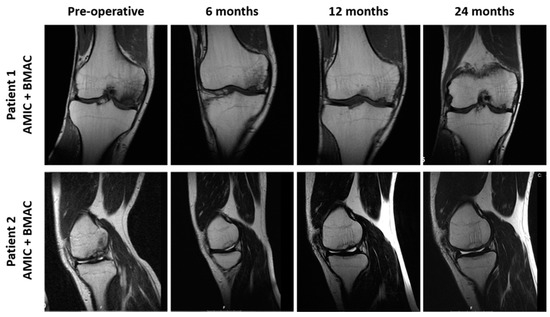

3.5. Radiological Observations